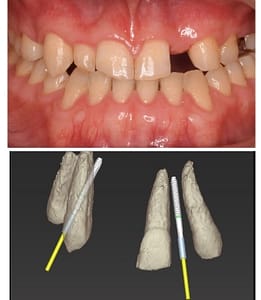

| 主訴 | 上顎側切歯および犬歯欠損 |

| 年齢 | 21歳7ヶ月 |

| 性別 | 女性 |

| 治療説明 | 上の歯、2番目の歯(側切歯)と3番目の歯(犬歯)が左右で先天性欠如をしておりました。 矯正治療で、2番3番目の歯の補綴物が入るスペースを確保。 その後インプラントを埋入し、補綴物を装着しました。 前歯部の先天性欠如の場合、骨が薄いケースが多くみられます。 こちらのケースも院長が開発した細いITインプラントを使用します。 |

| 治療期間 | 1年10ヶ月 |

| 資料提供 | ITデンタルクリニック |